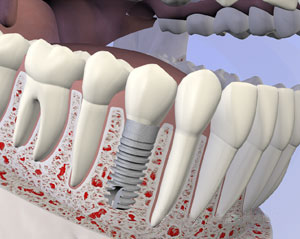

Single Tooth Dental Implant

This is the most common and simplest tooth replacement we perform. When a tooth is missing because of illness or a traumatic injury, the surrounding area is affected by the missing tooth. The adjacent teeth will shift out of alignment over time if the space is left empty. The jawbone will also deteriorate if the socket for the tooth root is empty.

A single-tooth dental implant starts with a titanium post being placed into the jaw socket where a tooth root used to be. Over several weeks, the jawbone will grow around and fuse to the implant, providing a sturdy base for the new tooth. After the implant is in place, a temporary cap will be placed.

When the implant and bone are strong and secure, a permanent crown, or artificial tooth, is attached to the implant with a screw. The look and feel are natural and comfortable. It can take three to six months for the jaw to heal sufficiently for the permanent tooth, but once it is in place, it can last a lifetime.